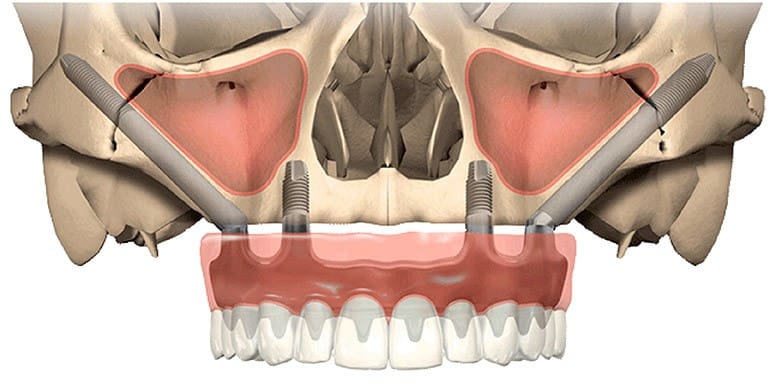

A diferencia de los implantes tradicionales, que se anclan en el hueso alveolar maxilar (el hueso donde estaban los dientes), los implantes cigomáticos se extienden y se fijan en el Hueso Cigomático (o Pómulo).

El hueso cigomático es una estructura densa y fuerte que nunca se reabsorbe, sin importar cuánto tiempo haya pasado desde la pérdida de los dientes.

En esencia: Si el suelo es demasiado blando para construir la casa, simplemente anclamos los cimientos a una roca sólida cercana.

- Atrofia Maxilar Severa: Pacientes con una reabsorción ósea tan avanzada que no permite la colocación de implantes convencionales, incluso después de un injerto de seno maxilar.

Debido a su proximidad a estructuras críticas (como la órbita del ojo y el seno maxilar), los implantes cigomáticos son considerados una cirugía de alto nivel de complejidad. No es un procedimiento que deba ser realizado por cualquier implantólogo.

- Diagnóstico 3D Riguroso: Uso indispensable de la Tomografía Computarizada (CBCT) para mapear la anatomía tridimensional del seno y el pómulo.